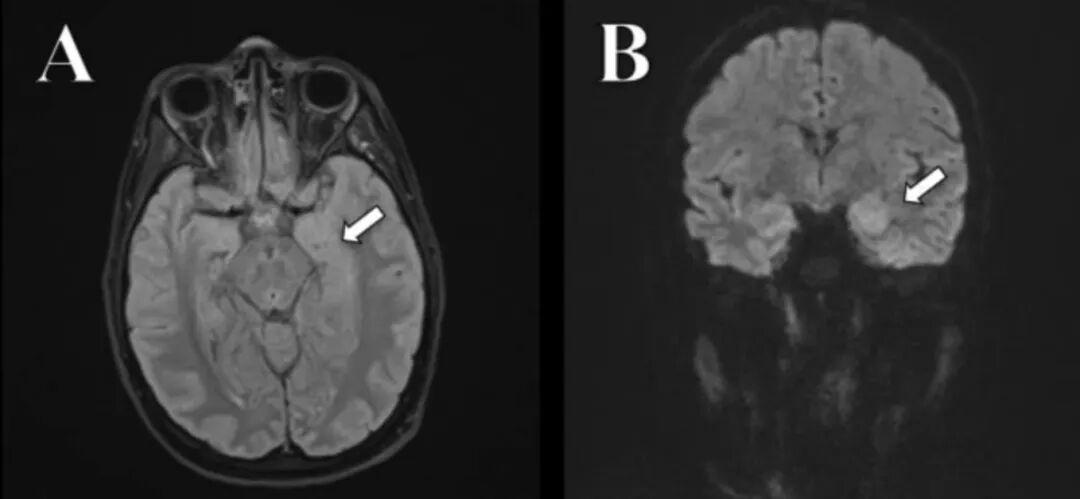

患者的海馬不對稱,出現了炎癥。圖片來源參考文獻